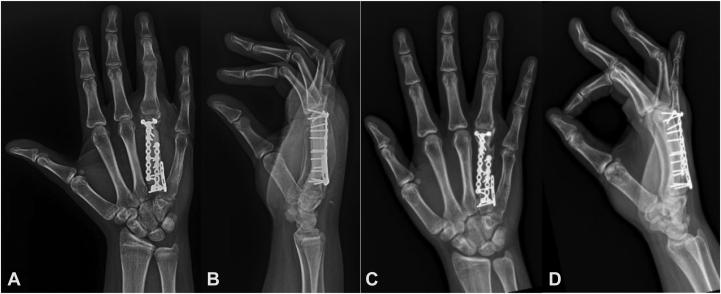

The two cases presented demonstrate the management of aneurysmal bone cysts of the metacarpal, which destroyed the normal bone architecture. Treatment of both cases included wide resection and metacarpal reconstruction with an intercalary fibular allograft. Denosumab use contrasts these two cases and is helpful in reestablishment of a cortical rim for fixation in the absence of a 1-cm margin proximally or distally to preserve the native carpometacarpal and metacarpophalangeal joints. Surgical resection and allograft reconstruction is a viable treatment for expansile metacarpal aneurysmal bone cysts, and neoadjuvant denosumab has utility in creating an ossified margin for fixation.

所呈现的这两个病例展示了掌骨动脉瘤样骨囊肿的治疗方法,该囊肿破坏了正常的骨结构。这两个病例的治疗均包括广泛切除以及采用腓骨中段同种异体骨移植进行掌骨重建。地诺单抗的使用与这两个病例形成对比,并且有助于在近端或远端没有1厘米切缘的情况下重建皮质边缘以进行固定,从而保留原生的腕掌关节和掌指关节。手术切除和同种异体骨重建是治疗扩张性掌骨动脉瘤样骨囊肿的一种可行方法,新辅助地诺单抗在为固定创造骨化边缘方面具有实用价值。